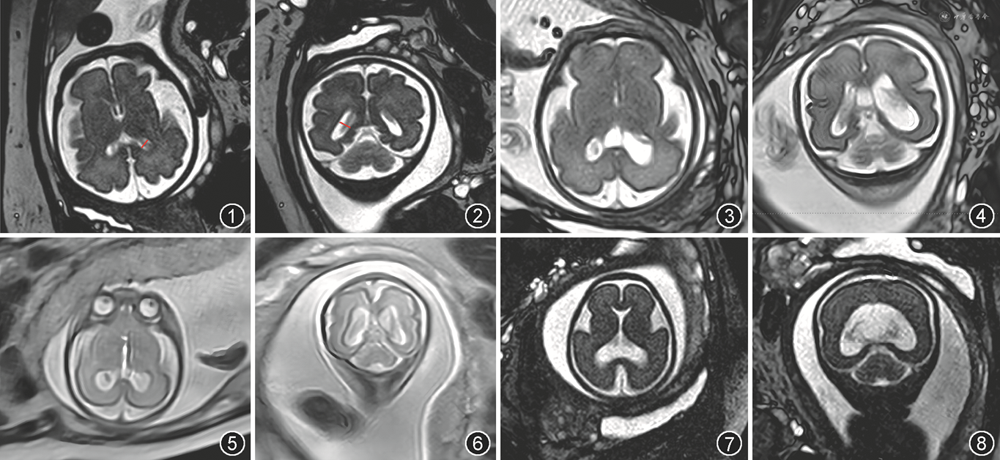

产前超声主要观测平面为轴位经侧脑室平面三角区脉络丛血管球水平,测量侧脑室体部、枕角和颞角汇合部的垂直内径,因其大小和结构在妊娠15~40周基本稳定,也通常是脑室扩张时首先扩张的区域。超声测量可能会受到近场伪影、胎位、颅骨骨化等技术限制,而胎儿MRI则不受干扰,测量结果与超声一致性很高。T2WI可以在胎儿脑部横断面和冠状面测量三角区垂直内径(图1,2),还可以测量侧脑室前角、体部、颞角或枕角等任何部位的内径;如果合并颅内结构异常,MRI能提供比超声更多的信息。研究显示MRI冠状面和超声轴位在侧脑室三角区测量的一致性均高于90%[5]。一项前瞻性多中心研究显示胎儿MRI提高了诊断脑异常的准确性,增加了对脑异常胎儿进行管理的信心[6]。

1.定性诊断:正常情况下脉络丛可基本填满侧脑室三角区,占50%~100%,与邻近侧脑室壁距离1~2 mm。脑室扩张时,脉络丛血管球在三角区所占比例明显下降,即“脉络丛变薄”,并向所属侧室壁垂落,称“脉络丛悬吊征”(图3,4)。定性诊断较为主观,轻度侧脑室扩张征象可能不明显。

产前超声或MRI能诊断侧脑室扩张,还能发现部分引起侧脑室扩张的病因,如脑出血、胼胝体缺如、前脑无裂畸形、中脑导水管狭窄等(图5, 6, 7, 8)。判断是孤立性或非孤立性脑室扩张,对于出生后新生儿总体预后评估有重要价值。神经系统中应评估脑室系统的形态、内容物及室周区域,确认有无异常信号、囊肿以及局灶性病变,详细评估透明隔、胼胝体、后颅窝、中脑导水管、脑实质、脑沟回及侧裂池等结构是否符合孕周等,是否存在感染、脑室出血、卒中等异常情况,尤其是晚孕期。最后,应评估胎儿体部及四肢等部位有无明确异常。